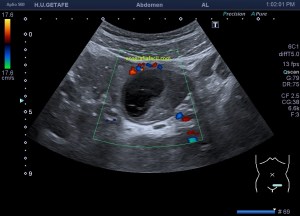

Bien, hemos visto una lesión que es un quiste hidatídico calcificado, pero te preguntarás, si nunca viste uno, ¿cómo es uno cuando tiene «hijas»?, es decir, cuando está activo…Mira este corte transversal de un hígado:

La LOE es de aspecto redondeado, heterogéneo, con multitud de pequeñas imágenes anecoicas e hipoecogénicas, de diferentes tamaños. Esta lesión fue estudiada también mediante otra técnica de imagen, la RMN donde se observa una imagen hiperdensa, con una amalgama de lesiones bordeando a periferia de la misma, de distintos tamaños como se objetiva en la imagen del mismo paciente, de la ecografía inmediatamente superior (Imagen 7). La lesión es activa, por tanto debió de ser tratada, la patología es potencialmente mortal en caso de que el quiste se rompiese.